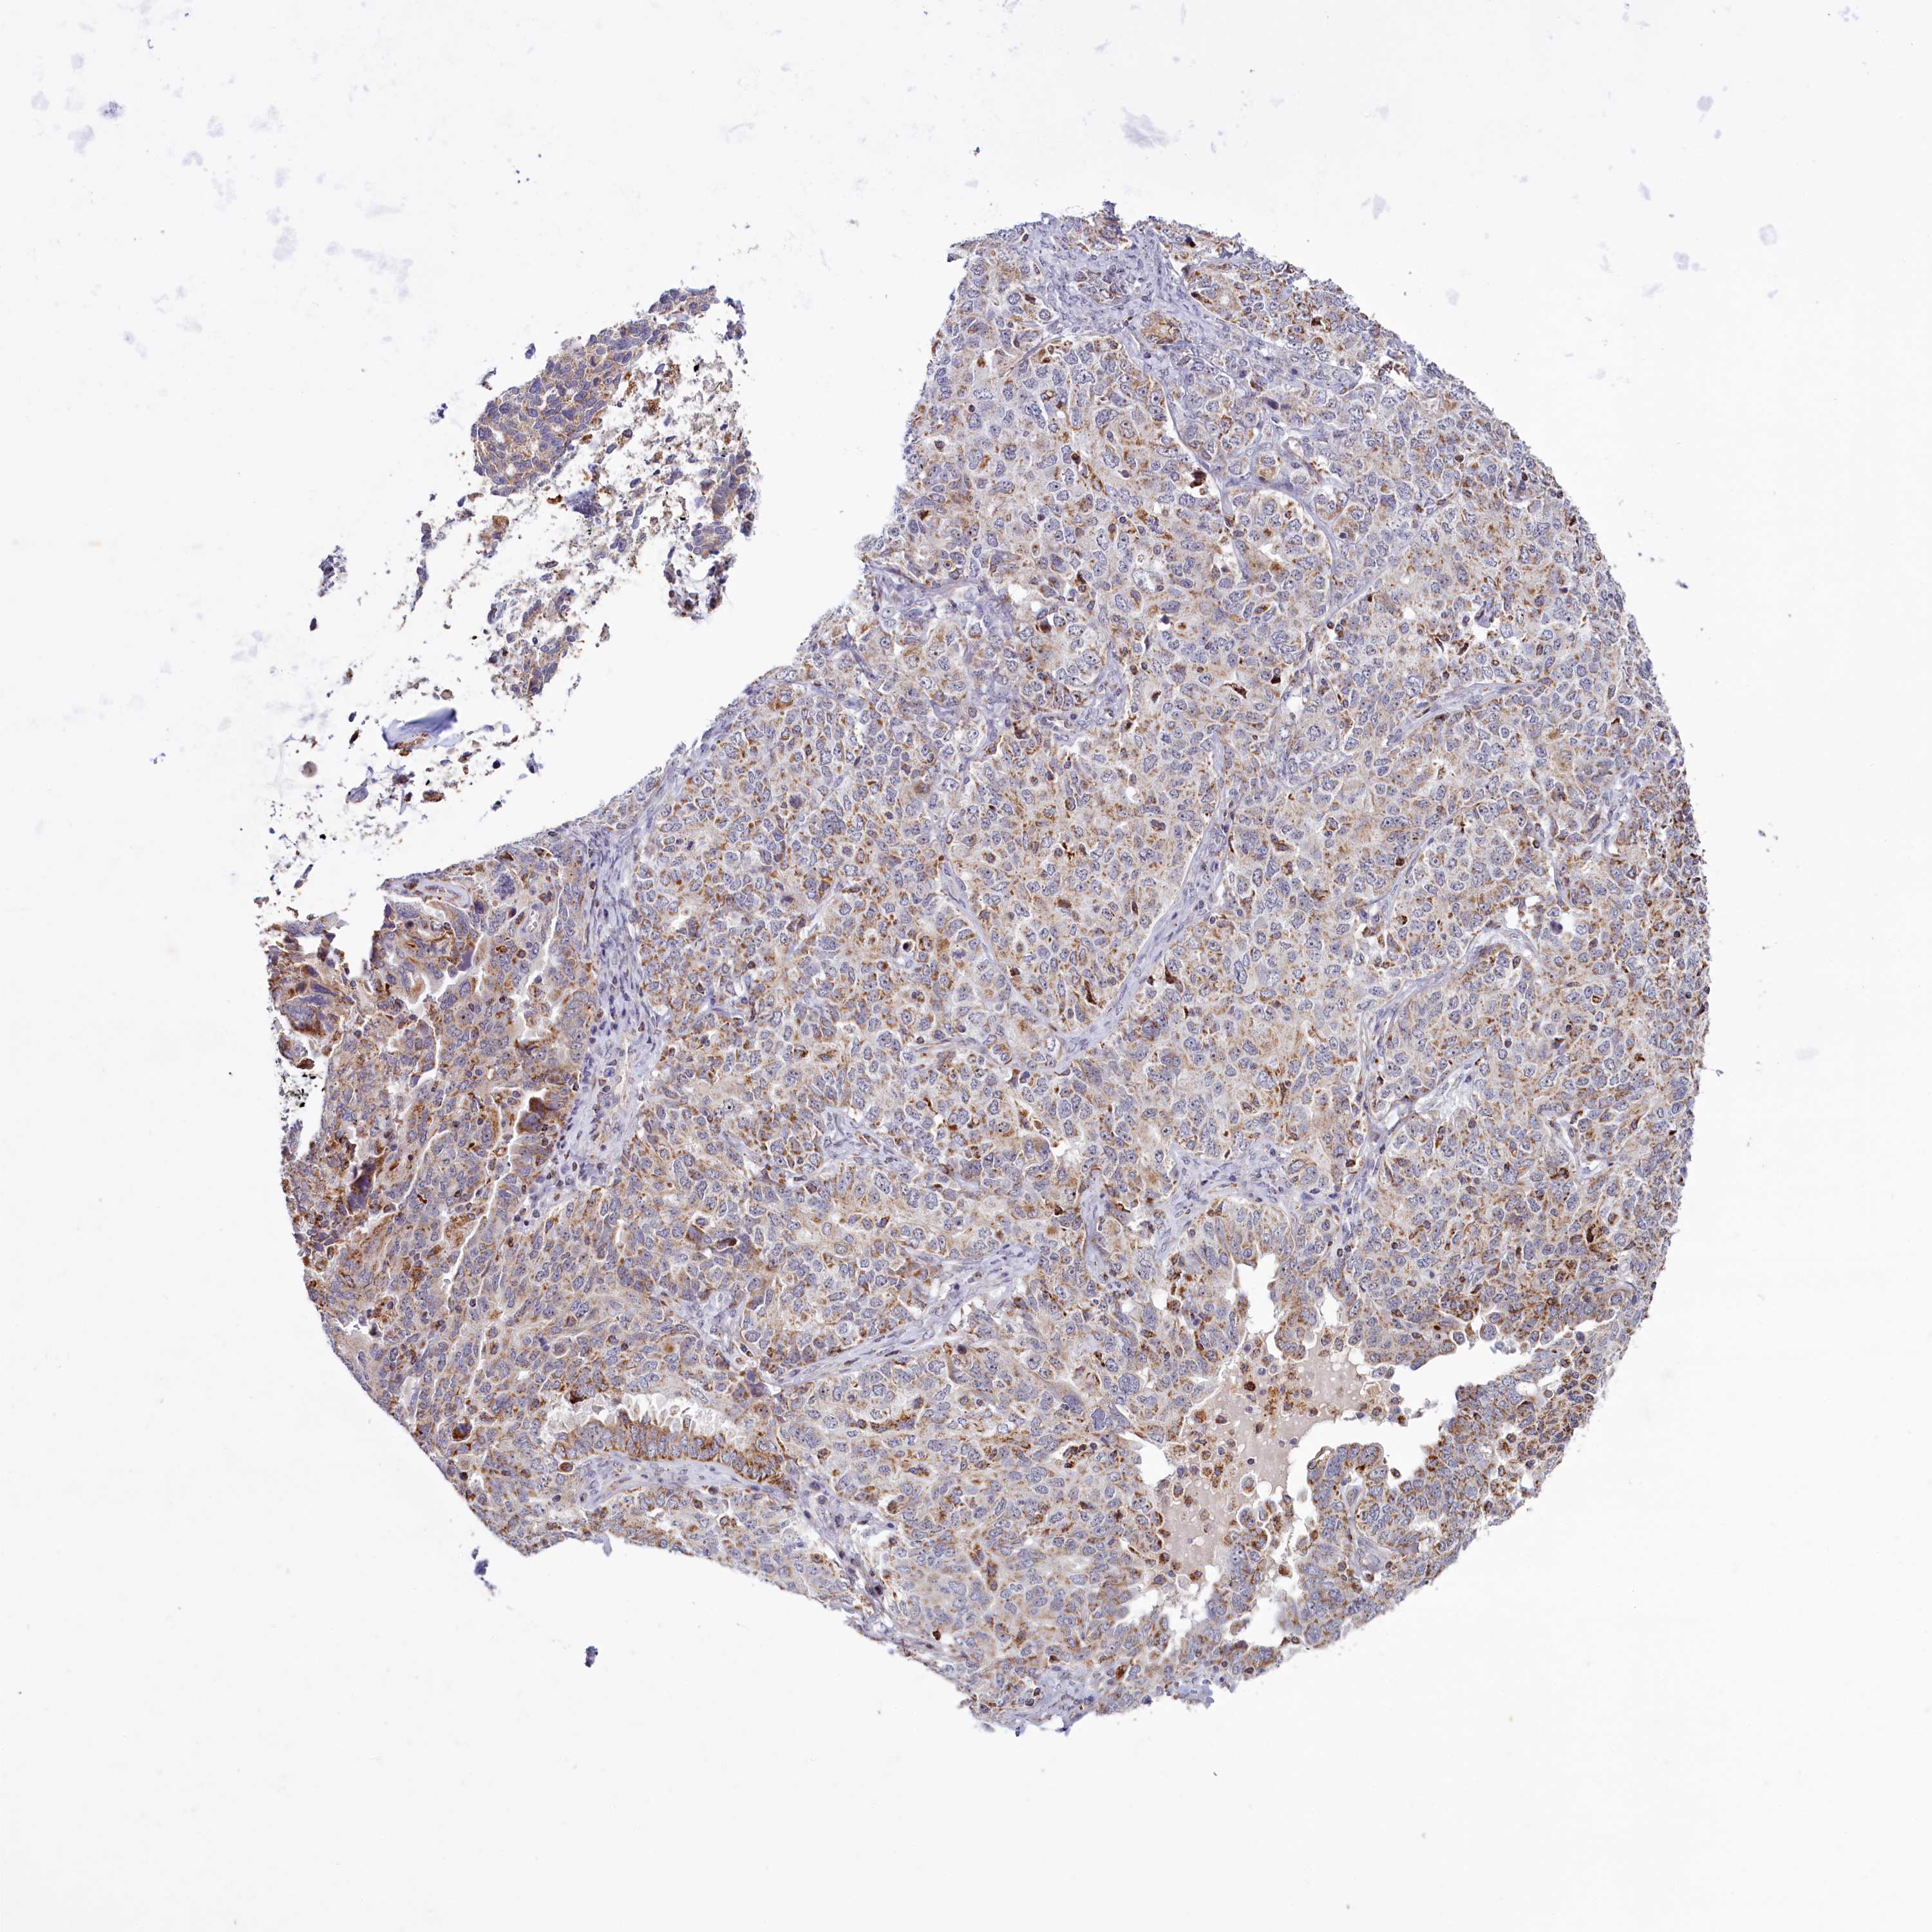

OVARIAN CANCER - Protein expressioni

A mouse-over function shows sample information and annotation data. Click on an image to view it in a full screen mode. Samples can be filtered based on level of antibody staining by selecting one or several of the following categories: high, medium, low and not detected. The assay and annotation is described here.

Note that samples used for immunohistochemistry by the Human Protein Atlas do not correspond to samples in the TCGA dataset.

Antibody stainingi

Antibody staining in the annotated cell types in the current human tissue is reported as not detected, low, medium, or high, based on conventional immunohistochemistry profiling in selected tissues. This score is based on the combination of the staining intensity and fraction of stained cells.

Each image is clickable and will lead to virtual microscopy that enables deeper exploration of all samples and also displays staining intensity scores, fraction scores and subcellular localization as well as patient and tissue information for each sample.

Antibody HPA039015

Antibody HPA039016

Cystadenocarcinoma, serous, NOS